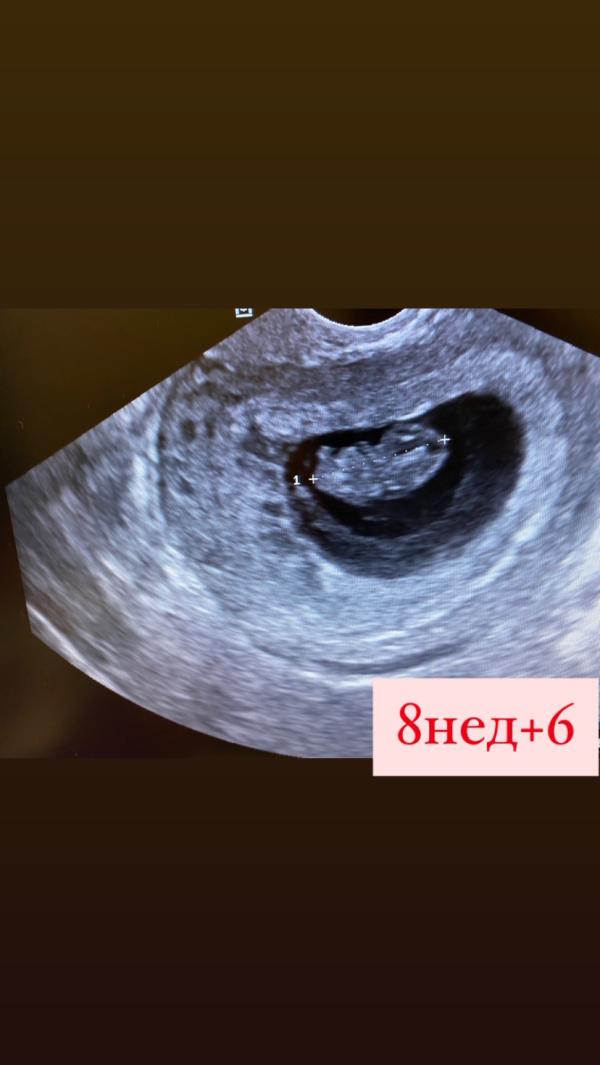

С каждым разом малышок на узи все интереснее!помню как радовалась точке в 4 недели😀а теперь думаю ну чему там можно было любоваться?)))ведь теперь уже начинает виднеться человечек,ручки,ножки и т.д,но рассмотреть уже можно))